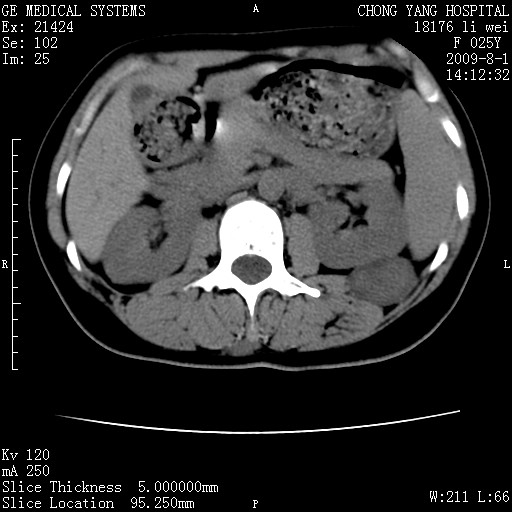

以下是引用pujunzhi在2009-8-1 20:23:00的发言:[br]胸椎旁及背部肌间良性病变,范围广,边界清,沿肌间生长,考虑淋巴管瘤、血管瘤,建议增强扫描。